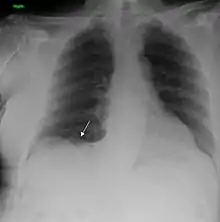

| A chest X-ray showing a tumor in the lung (marked by arrow) | |